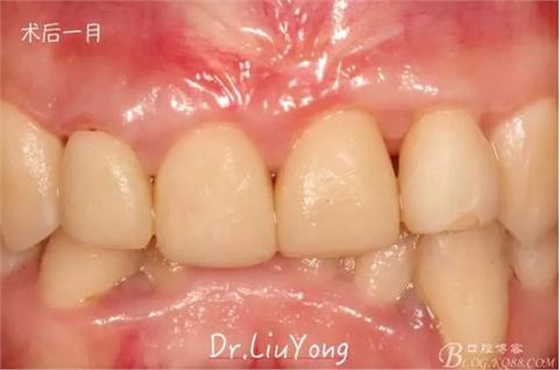

臨時修復體戴入后1月,復查,唇側觀如上圖

手術后1月,決定先行臨時修復,由于患者為重度深覆合,因此考慮將上前牙通過臨時修復體,降低切端的高度,減輕覆合,同時將舌傾的牙冠形態(tài)調(diào)整為較為直立。B2為根折到齦下1.5mm,考慮到患者無法接受正畸,同時如果近中鄰面行冠延長手術會帶來后續(xù)的黑三角美觀問題,因此選擇在橡皮障下行齦壁提升,然后A2纖維樁+樹脂核,A1-B2臨時樹脂貼面修復,A2臨時冠修復。